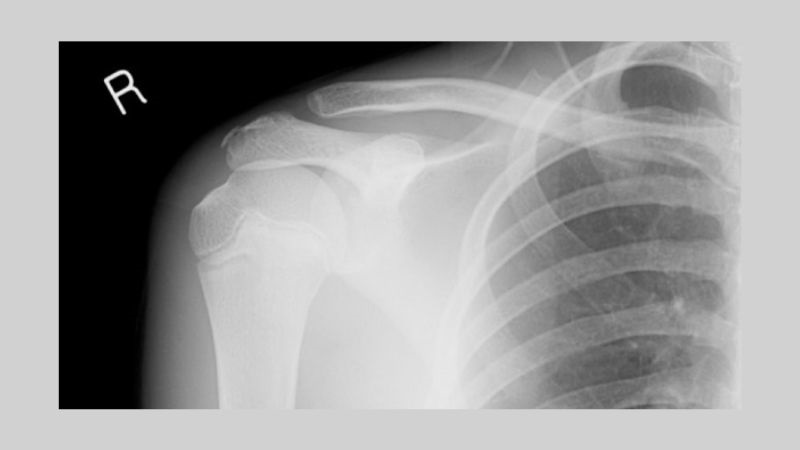

Theo thống kê thực tế, trung bình cứ 10 trường hợp gãy đầu trên của xương tay thì có 6 người bị gãy cổ phẫu thuật xương cánh tay. Điều này cho thấy đây là một dạng sang chấn thường gặp và chúng thường có xu hướng gia tăng theo độ tuổi.

Gãy cổ phẫu thuật xương cánh tay được hiểu là gãy phần đầu trên xương cánh tay bao gồm cả cổ phẫu thuật và cổ giải phẫu.